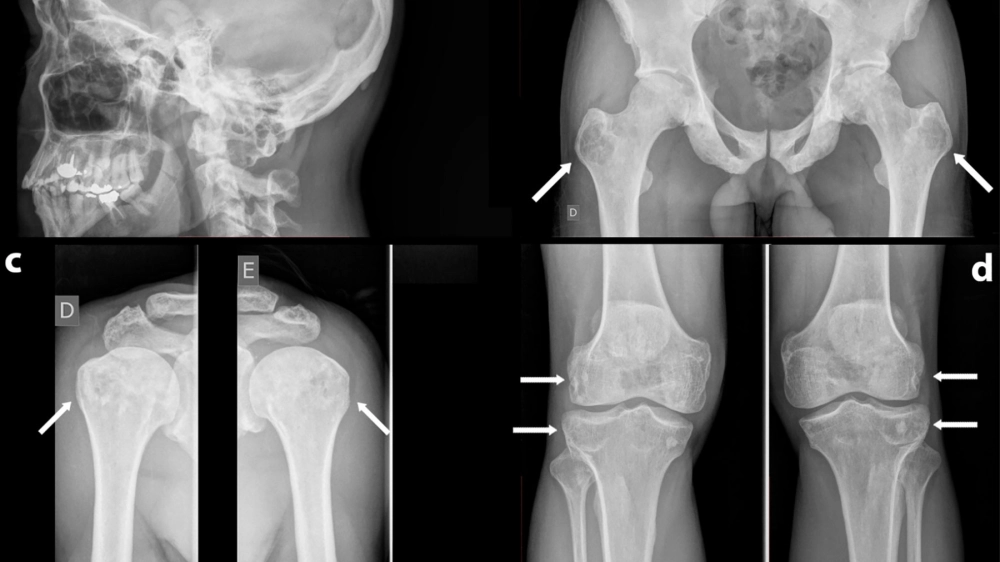

• Triệu chứng bệnh Paget xương phổ biến nhất là đau xương. Xương có thể bị biến dạng, cong vẹo, dễ gãy và gây chèn ép các dây thần kinh.

• Các triệu chứng khác có thể bao gồm da ấm hơn ở vùng xương bị ảnh hưởng, đau đầu, giảm thính lực nếu bệnh Paget ảnh hưởng đến xương sọ.

X-quang cho thấy sự biến dạng của bệnh Paget xương

Hộp sọ bị ảnh hưởng bởi bệnh Paget xương